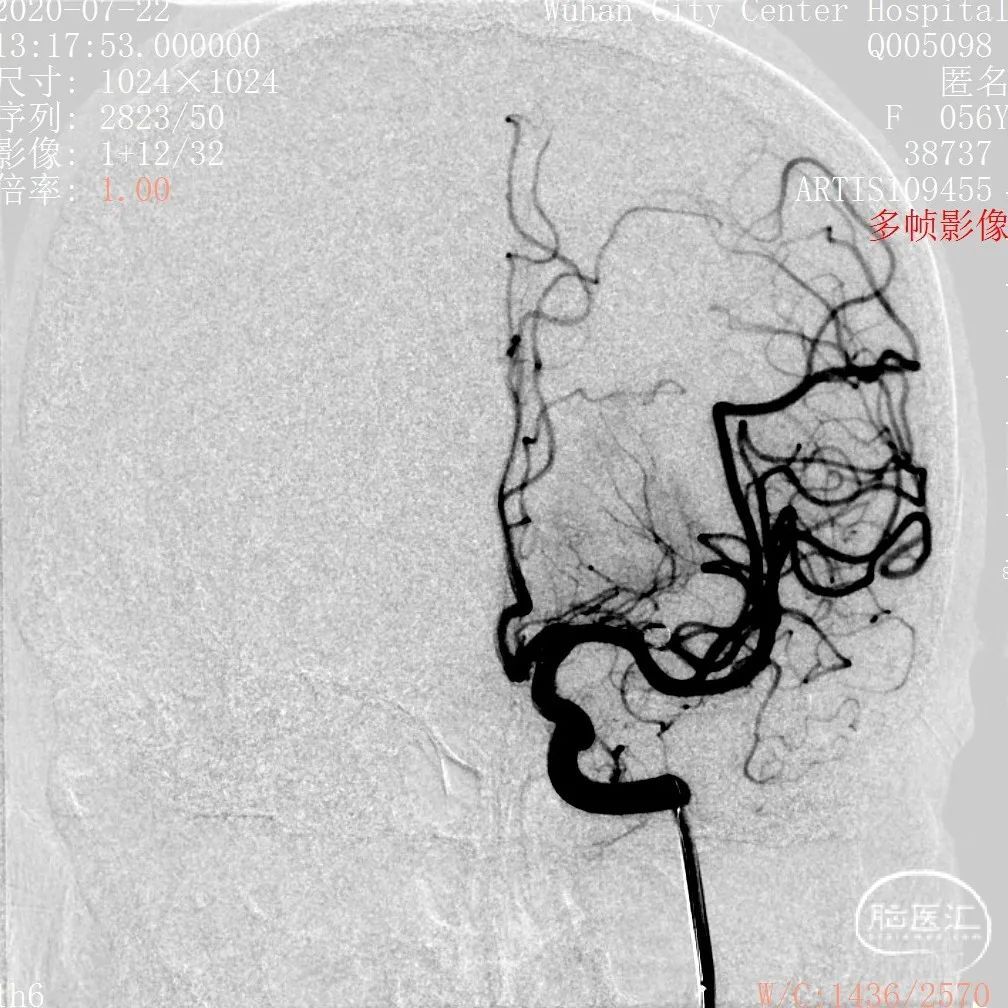

DSA 2020-07-22

3D和测量